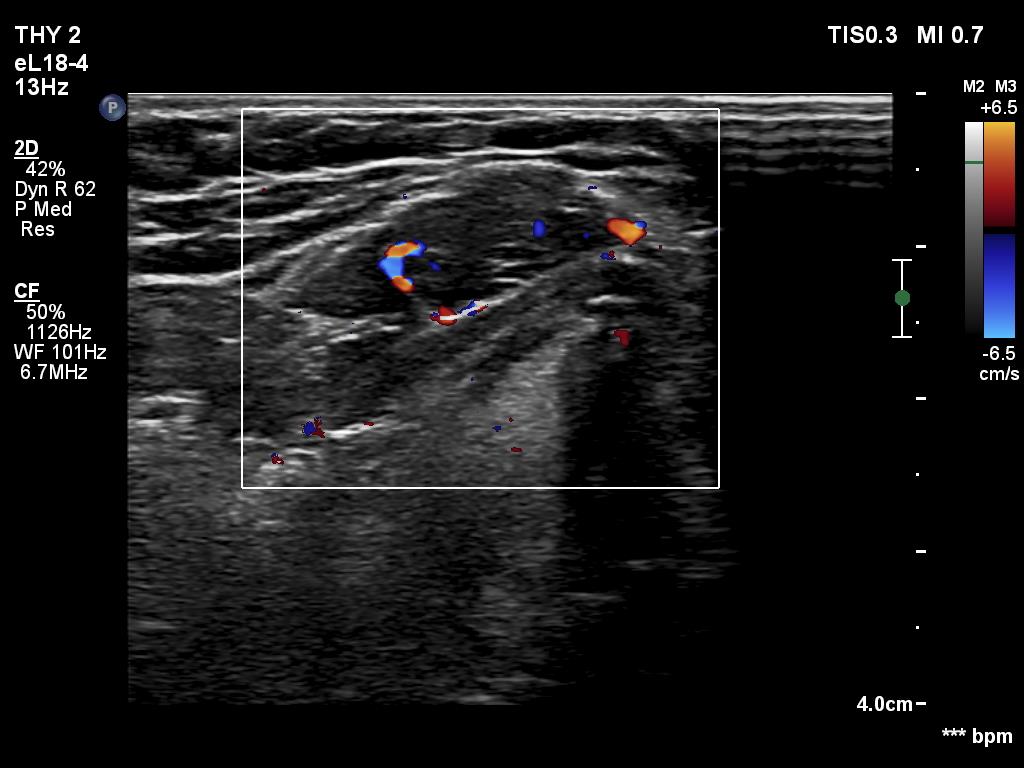

Follow-up investigation 6 months after first visit (ultrasonographic picture 7)

Middle part of the neck, 4 cm above the thyroid, longitudinal scan, color Doppler mode. The aberrant tissue has vascularization which would be an unusual finding in muscle tissue.